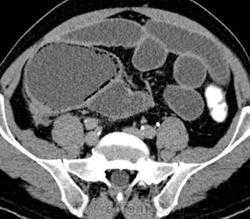

Однако наиболее распространенным является применение КТ для диагностики и дифференциальной диагностики очаговых поражений печени и поджелудочной железы. Стандартным является выполнение КТ с болюсным введением 100-140 мл контрастного средства. Многофазное исследование в различные фазы контрастирования (из которых важнейшими являются артериальная и портально-венозная) позволяет выявлять и характеризовать очаговые поражения печени и поджелудочной железы, планировать лечение и оценивать его результаты. С помощью МСКТ можно с высокой точностью визуализировать артерии и вены органов брюшной полости, а также желчные протоки.

Благодаря быстроте и надежности МСКТ все чаще используется при обследовании пациентов с диагнозом «острый живот» (выявление перфорации полых органов, кровотечений, кишечной непроходимости, мезентериальной ишемии, острого аппанедицита, панкреатита, холецистита и другой патологии).